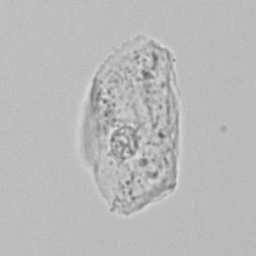

Squamous

In women, squamous epithelium is located at the base of the bladder and urethra, in men at the end of the urethra and foreskin. In addition, they line the inside of the vagina and perineum. Finding a small amount of squamous cells in urine is normal because these cells are constantly being renewed and replaced. Large amounts are usually caused by urine being collected after it has run down nearby areas such as the vagina, perineum or foreskin; this is referred to as contamination.

Sometimes these epithelial cells contain conspicuous dark granules; keratohyaline granules. These contain substances that contribute to the cornification of the skin layer. Their presence is normal and should not be confused with bacteria.